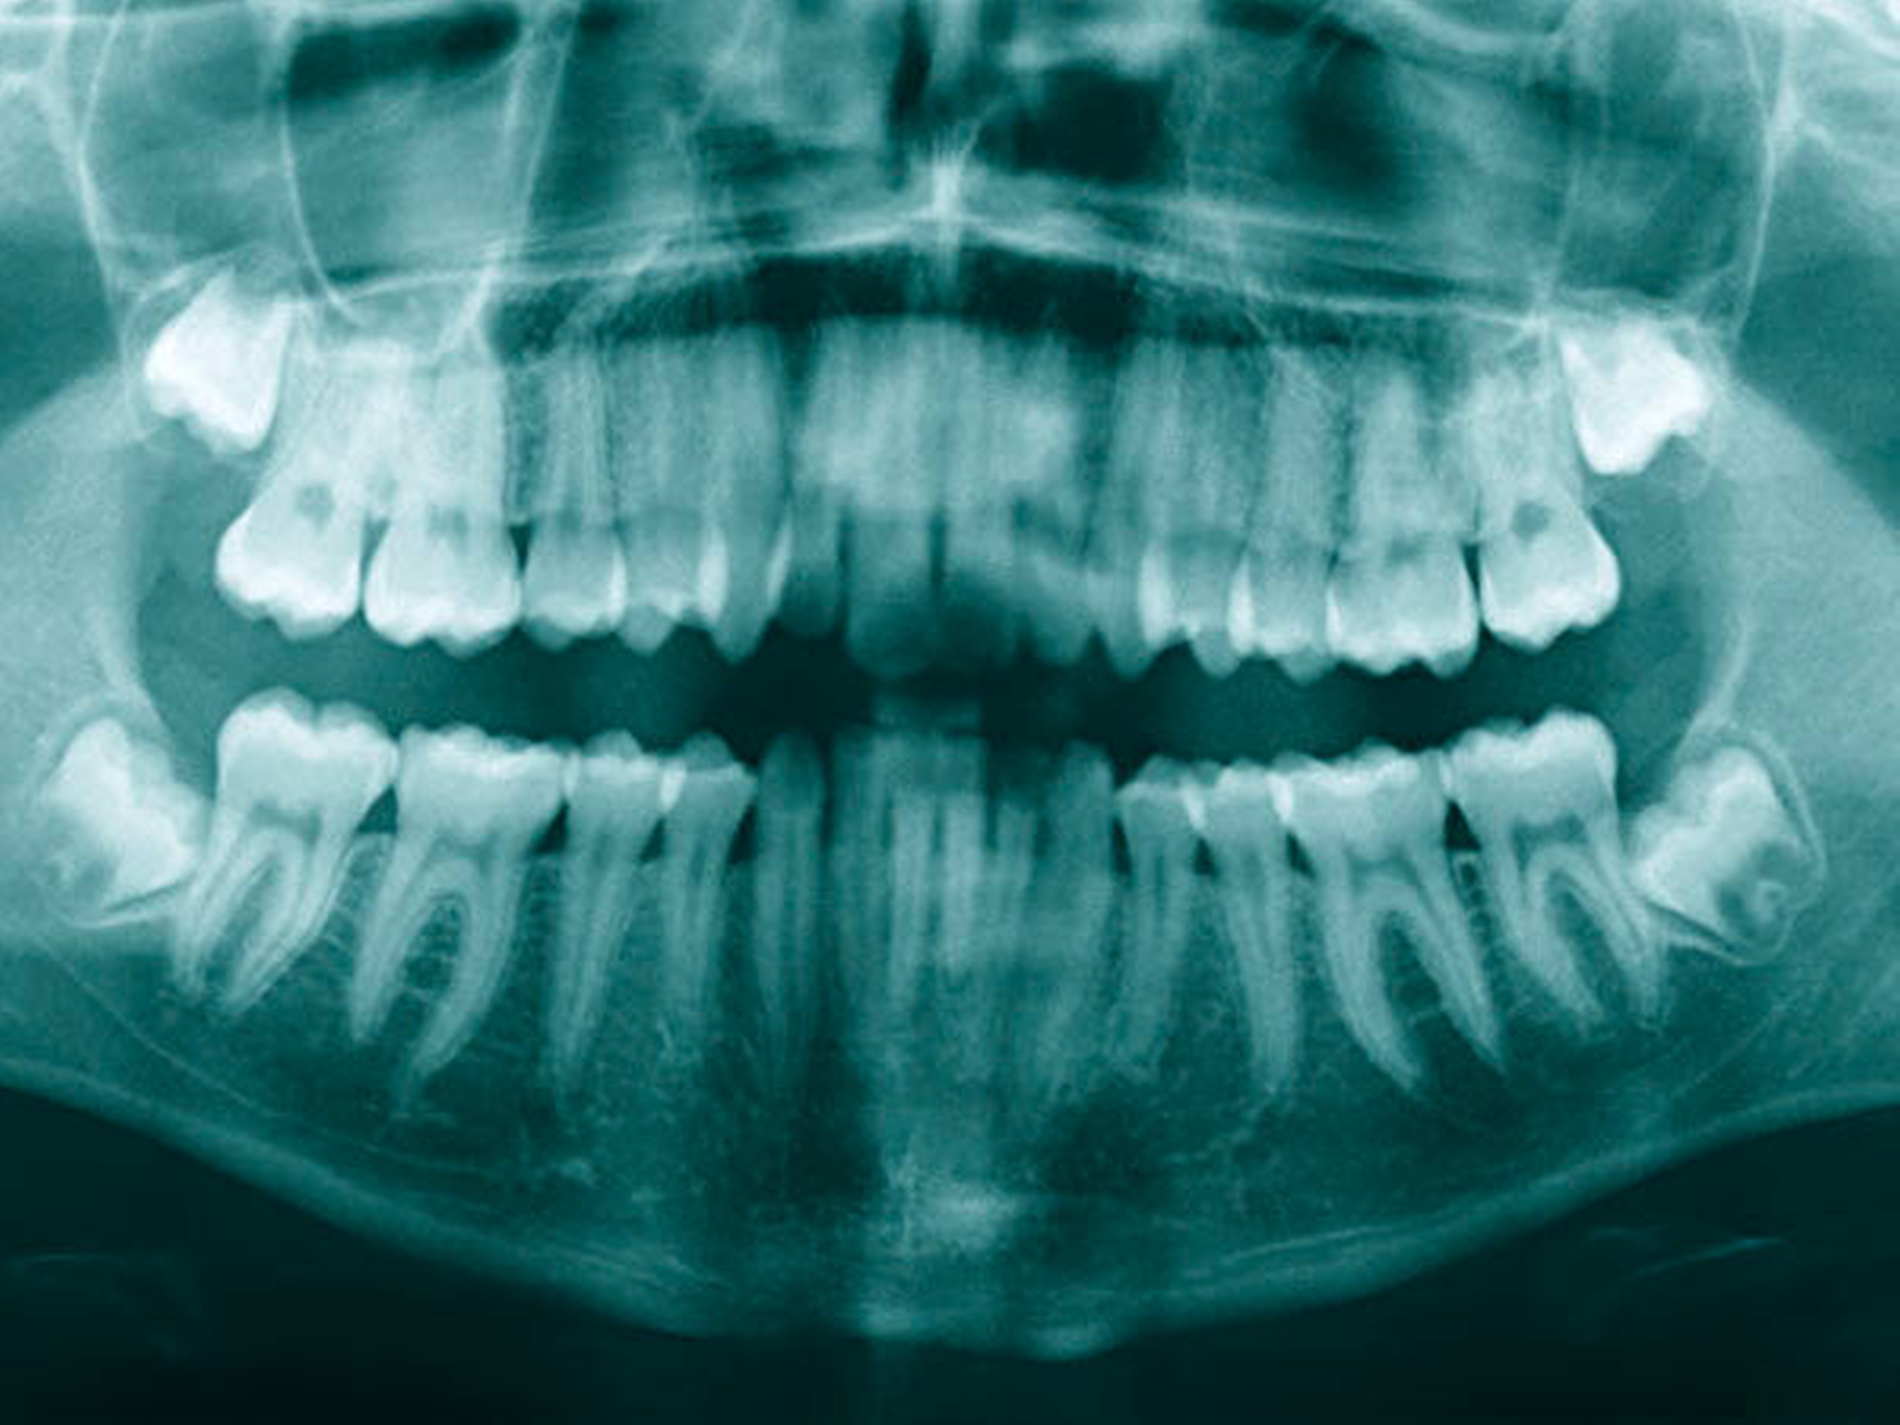

Ein 16-jähriger gesunder Patient stellte sich – überwiesen vom Vorbehandler – mit einem intraoperativ in das lingual gelegene Weichgewebe dislozierten Zahn 38 zur Therapieübernahme in der Klinik vor. Anamnestisch sollten aufgrund eines relativen Platzmangels alle Weisheitszähne entfernt werden (Abbildung 1). Der Eingriff war in einem zweizeitigen Vorgehen mit der Osteotomie je einer Kieferseite geplant gewesen. Nach der komplikationslosen Osteotomie des Zahns 28 wurde der Zahn 38 dargestellt. Dieser dislozierte im Verlauf der Entwicklung jedoch ins linguale Weichgewebe. Die sofortige Bergung scheiterte, woraufhin zur besseren Lokalisierung eine digitale Volumentomografie (DVT) angefertigt wurde. Hier zeigten sich eine hoch-mandibuläre Verlagerung nach lingual unterhalb des Nerveneintritts des N. alveolaris inferior sowie die Fraktur der lingualen Knochenlamelle (Abbildungen 2 und 3). Im Praxisumfeld war bei der gegebenen Dislokation eine sofortige Bergung nicht ohne ein erhöhtes Risiko der Nervschädigung möglich, so dass der Patient für eine Entfernung in Intubationsnarkose in die Klinik überwiesen wurde. Bei Aufnahme ließ sich eine Hypästhesie der linken Unterlippe und des Kinns sowie der linksseitigen Zungenspitze mit einer Einschränkung des Geschmacksinns nachweisen. Enoral zeigte sich eine reizfreie, frische Wunde im Bereich der linken Retromolar-Region im Oberkiefer und eine adaptierte reizfreie Wunde regio 37–38 im Unterkiefer.